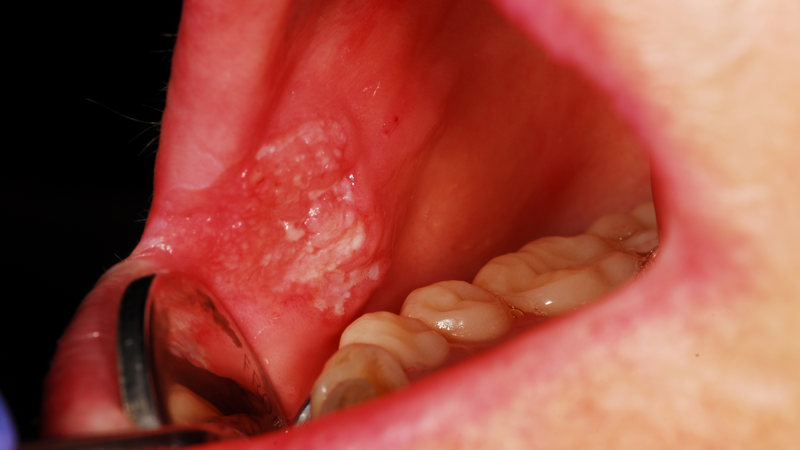

Bệnh bắt nguồn từ tế bào vảy ở lớp ngoài cùng của da, tức là lớp biểu bì. Thông thường, ung thư biểu mô tế bào vảy phát triển ở các vùng da tiếp xúc trực tiếp với ánh nắng mặt trời như đầu, cánh tay và chân. Ngoài ra, nó cũng có thể xuất hiện ở các vùng có niêm mạc, tức là lớp lót bên trong của cơ thể như miệng, phổi và hậu môn.

Ngoài ra, ung thư tế bào vảy có thể xảy ra ở niêm mạc như miệng, hậu môn, phổi. Tùy thuộc vào vị trí mà triệu chứng có thể khác nhau, ví dụ như ung thư tế bào vảy ở miệng có thể gây ra các triệu chứng như:

Hai yếu tố nguy cơ chính của ung thư tế bào vảy ở miệng là hút thuốc lá và sử dụng rượu. Một số tình trạng khác làm tăng nguy cơ ung thư tế bào vảy ở miệng như nhai trầu, lạm dụng nước súc miệng, nhiễm HPV ở miệng (tiếp xúc sinh dục - miệng).